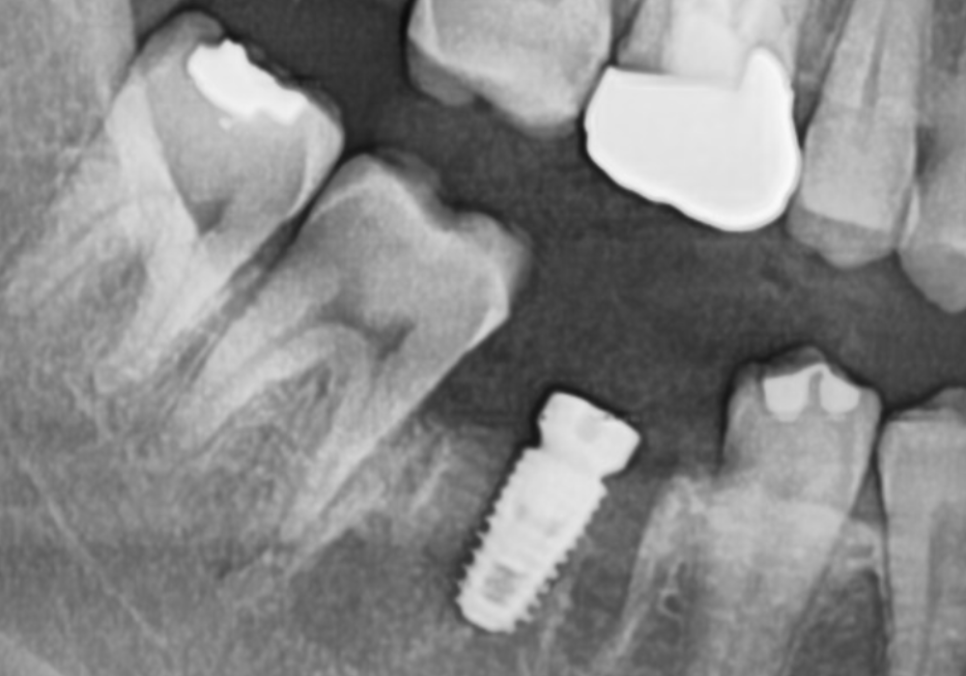

엑스레이와 3D CT로

정밀 검사를 진행해 보니,

치아 사이에서 시작된 충치가

치아 내부 상아질을

이미 광범위하게 녹인 것을 확인할 수 있었습니다.

그 뿐만 아니라, 뿌리 끝에 까~맣게

염증이 비춰보이네요

빨간색으로 표시한 부분이

주요 신경인 '하치조 신경'인데,

거의 맞닿아 있을 정도로

염증이 많이 퍼져있는 게 보이시나요?

안타깝지만, #46 치아는

서둘러 발치를 진행해야 했습니다.